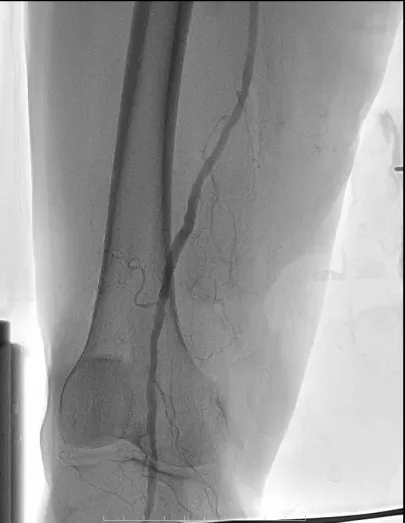

手术前右下肢动脉闭塞

右下肢动脉取栓后动脉显影

10月19日,一场生命保卫战在多学科护航下展开。介入手术室团队为患者实施了精准的监护与管理,竭力维持其血流动力学稳定。在先进的DSA引导下,介入血管外科团队通过微创穿刺,将取栓导管精准送达堵塞部位。一个长约10厘米的暗红色血栓条被成功取出体外。复查造影显示,右腿血供被成功重建!